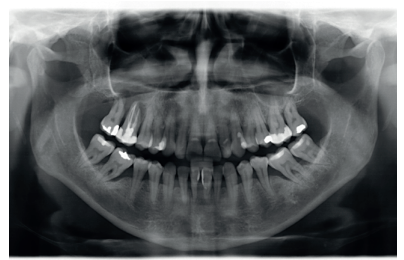

This was the case of a 58-year-old female patient who attended the dentist practice to assess the 16th and 17th molars for pain and mobility. On clinical examination, mobility of both was observed with suppuration at the level of the sulcus. Radiography confirmed our diagnosis of considerable bone loss and sinus perforation at the apex of both molars (Figure 2).